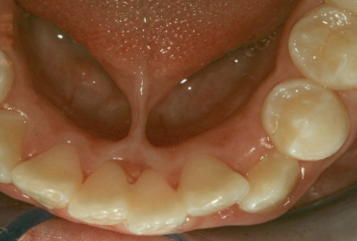

minimal manifestation of CP

bifid uvula

surface is intact but defect exists in the underlying musculature of the soft palate

submucous palatal cleft